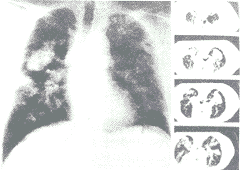

图4 有结节影病人的胸片及CT片。胸片及CT均可见异常,但肺上叶的团块影只有CT检查才能发现

图2和图3显示经X线平片和CT两种方法检查对于小结节和融合团块的检出在多数情况下是一致的。图4显示个别经CT检查发现的融合团块经X线平片检查并未见有融合团块。

胸部CT和X线平片均可检出矽肺的融合团块(图3),但是CT检查较X线平片检查可发现更多的有融合团块的复杂矽肺病例,在本研究中经CT检查发现有47%病例为复杂矽肺,而经X线平片检查只发现有38%的病例为复杂矽肺。在X线平片检查未见融合团块的病例中,有5名经CT检查发现有融合团块存在(图4)。这点对于临床非常重要,因为这些团块有可能是矽肺早期的融合团块,也可能是结核或者是其他的肺部病变,如肺癌,而肺癌也是该年龄组较常见的一种疾病。在CT检出的5例融合团块病例中,有1例为肺癌,4例为矽肺融合团块。对融合团块的早期检出也很重要,因为这些融合团块以无功能的纤维团块代替了正常的肺组织,与呼吸系统症状的出现及肺功能恶化都密切相关[2]。此外这些复杂矽肺的预后也较单纯矽肺差[3]。